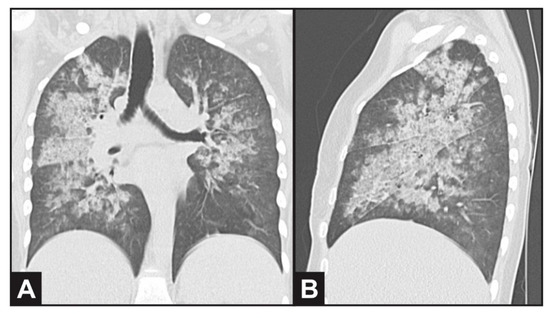

Ultrasound revealed normal-sized kidneys with preserved echogenicity. A chest CT scan evidenced bilateral and diffuse ground-glass opacities (Figure 1), thickening of intralobular septa and luminal filling in the bronchial walls, compatible with alveolar hemorrhage. She was prescribed antibiotics (ceftriaxone and clarithromicin) due to possible bacterial infection. Serum immunodiffusion for fungi was negative (Paracoccidiodes brasiliensis, Aspergillus fumigatus and Histoplasma capsulatum). Bronchial washing results were negative for viruses, bacteria, mycobacteria and fungi, revealing the presence of bloody fluid in the respiratory tract.

Figure 1. Computed thorax tomography evidencing bilateral and diffuse ground-glass opacities in (A) coronal and (B) sagittal plane view, compatible with alveolar hemorrhage.